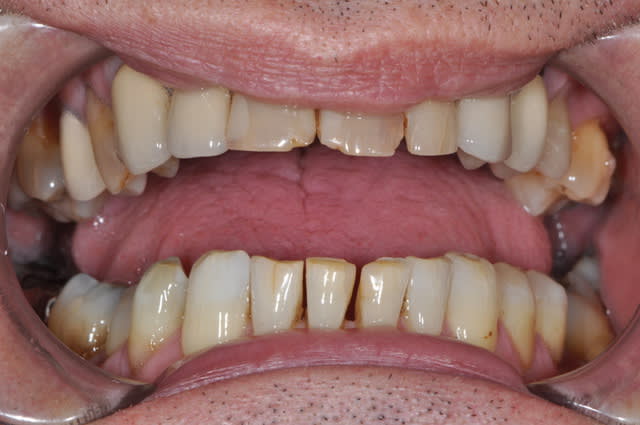

ce patient a une demande essentiellement esthétique,

que me conseilleriez-vous au niveau

des incisives supérieures ?

11 et 21 sont vitales.

effectivement pour le bas traitement à minima,

éclaircissement en cours puis réalisation de composites proximaux,

pour le haut je ne suis pas sur que la forme de la 12 soit très esthétique,

ainsi est-ce que refaire la 12 et cc pour 22 21 11 parait pertinent ?

sauf que si on refait 12 en gardant l'inlay-core ( je suis toujours prudent avec les déposes !!), cela vaut-il le coup de faire des cc ?